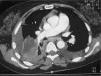

Observaciones clínicasCaso 1Varón de 45 años, exfumador (30 paquetes/año), bebedor de 30g de alcohol al día, con antecedentes de hipertensión arterial y fibrilación auricular de reciente diagnóstico. Ingresó por cuadro de 25 días de evolución consistente en fiebre, dolor en el costado derecho de tipo pleurítico, escalofríos y malestar general. En la exploración destacaban obesidad y semiología de derrame pleural derecho. La radiografía de tórax y la tomografía computarizada (TC) mostraron derrame pleural derecho, loculado, con pleura visceral engrosada y condensación subyacente en el lóbulo inferior derecho (fig. 1a). Se realizó una toracocentesis diagnóstica y se obtuvo un líquido purulento, verdoso, con olor pútrido, en cuyo cultivo creció G. morbillorum sensible a penicilina, cefalosporinas y aminoglucósidos. Se instauró tratamiento con tubo de drenaje torácico (volumen total de 1.200ml), fibrinolíticos y cefotaxima a dosis de 1g cada 6h por vía intravenosa (i.v.), junto con levofloxacino (500mg cada 12h, i.v.), durante 16 días. Posteriormente, se añadió cefuroxima (500mg cada 12h por vía oral) hasta completar 26 días. En una revisión posterior se apreció un mínimo engrosamiento pleural basal en el pulmón derecho de carácter residual. Durante su ingreso presentó un absceso perianal que precisó drenaje quirúrgico, del que no se remitieron muestras microbiológicas.

A) Radiografía posteroanterior de tórax del caso 1, en la que se aprecia un derrame pleural derecho, loculado, con pleura visceral engrosada y condensación subyacente en el lóbulo inferior derecho; B) Tomografía computarizada de tórax del caso 2, que muestra derrame pleural izquierdo, loculado, que forma 3 colecciones, y adenopatías mediastínicas patológicas.